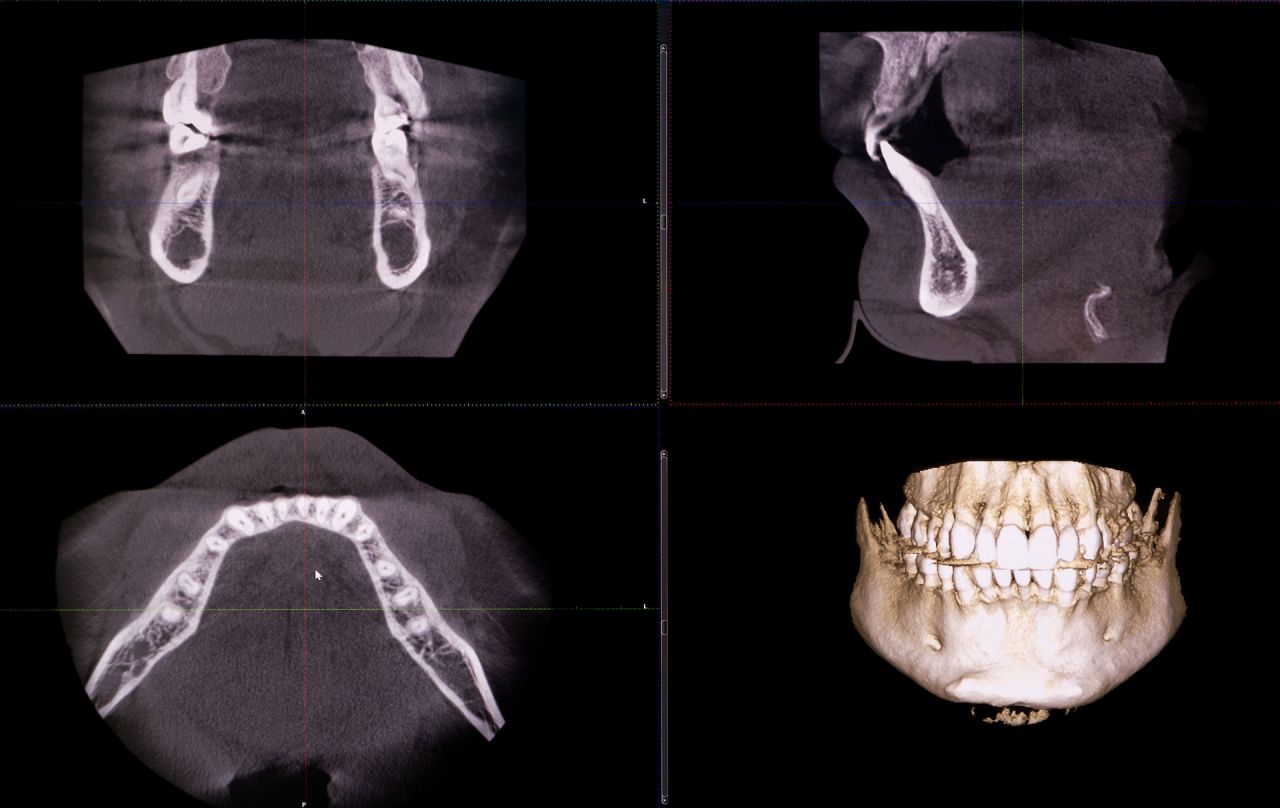

Mit dem strahlungsarmen Verfahren der digitalen Volumentomographie (DVT) können in vielen zahnmedizinischen Bereichen diagnostische Fragestellungen wesentlich besser beantwortet werden als mit klassischen Röntgenaufnahmen. Die Vorteile der DVT sind ebenso vielfältig wie die Anwendungsgebiete:

- Die natürlichen anatomischen Gegebenheiten werden detailreich, maßstabsgetreu und nicht verzerrt dargestellt.

- Eine Behandlung bzw. ein chirurgischer Eingriff kann mit den dreidimensionalen Aufnahme sicherer geplant und durchgeführt werden.

- Im Vergleich zu der sonst für solche Aufnahmen verwendeten Computertomographie ist die Strahlendosis deutlich geringer.